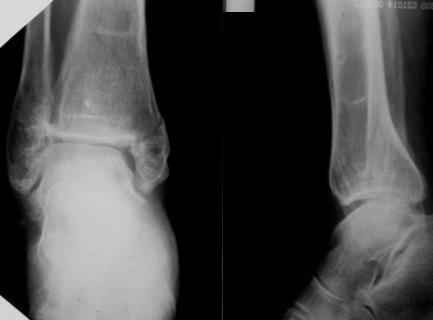

Посмотрели снимки после репозиции - не понравилась зона синдесмоза.

Сделали 3/4-е - впечатление, что в 99-том там что-то было. На

5.11.09г. запланирована КТ.

На сегодня остаются, хотя и в более осторожной формулировке, вопросы

по дальнейшему лечению:

1. С учетом анамнеза и развалившегося метаэпифиза, можно-ли

надеяться на консолидацию если оставить все "как есть"?

2. Если "нет", то каков рациональный объем хирургической агрессии?

3. Следует-ли считать правомерным следующее предположение:

"Отказавшись от операции сейчас, под давлением аргументов об

удовлетворительном стоянии отломков, мы упускаем время для

остеосинтеза, а через три месяца, констатировав несращение,

вынуждены будем планировать артродез в гораздо менее благоприятных

условиях."